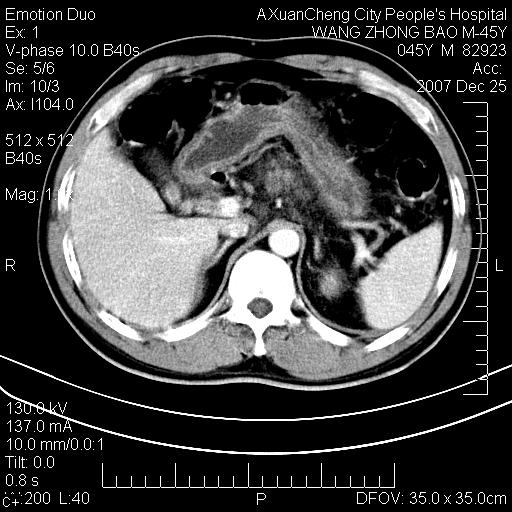

以下是引用卜一在2007-12-25 14:07:00的发言:[br]胰头钩部略增大,与十二指肠壶腹部关系密切,其内明显见软组织密度肿块,明显强化,但肠壁较光滑 柔软。考虑:炎性增生!建议消炎后复查!待除外壶腹部腺癌!

以下是引用zjzjr在2007-12-25 13:35:00的发言:[br]考虑正常的十二指肠乳头部,建议胃镜检查.

以下是引用qiuleiyu在2007-12-25 18:14:00的发言:[br]胰腺增大,周边渗出改变,肾前筋膜明显增厚,示少量积液.胆囊壁毛糙,周边少许渗出,胆总管壁厚,异常强化,然扩张不明显.结合病程急短;考虑;胆管炎,胆囊炎,胆源性胰腺炎可能大,请结合实验室检查及随访.

以下是引用lisihao在2007-12-25 14:23:00的发言:[br]急性水肿型胰腺炎[br]依据:1、胰腺弥漫性肿大,边缘稍毛糙;[br] 2、双侧肾周筋膜增厚,尤以左侧为甚(重要征象)[br] 3、双侧后胸膜增厚(刺激性炎症);[br] 4、结合病史,查血尿淀粉酶应该可以确诊。